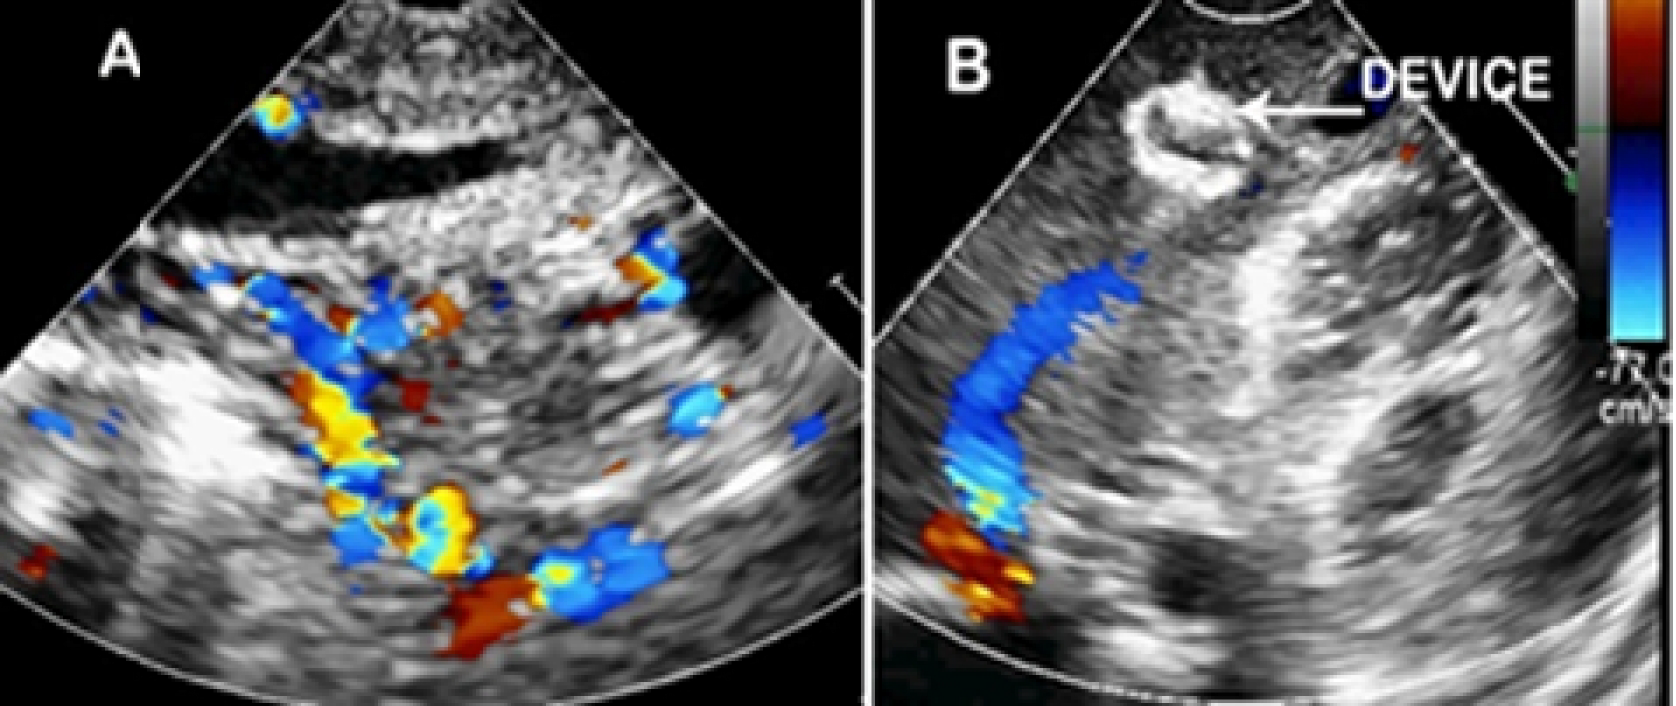

Terumo catheter. Almost complete cessation of flow through the anomalous channel was achieved by instillation of PVC particles at the end. The care was taken so that the diluted contrast containing PVC particles did not reflux into the celiac plexus. Once the check angiogram showed good occlusion of the mass, the ADO II device was released. Post procedure angiogram showed no flow into the hepatic lesion from the arterial end and the device was in good position at the venous end (Fig. 2D). The highly vascular lesion before procedure (Fig. 3A) regressed completely post procedure with the device in situ (Fig. 3B). The patient developed distension of upper abdomen after the procedure. This was treated conservatively as peristaltic sounds were well heard and the patient recovered within 48 hours. Post procedure there was also a local complication with loss of pulse in right femoral artery. This was treated with intravenous heparin infusion for 24 hours followed by intravenous heparin 8th hourly for 72 hour, till the pulse was well felt and there were good Doppler signals. This led to reappearance of vascular channels in the lesion on abdominal ultrasound. But the CT angiogram done after 3 months showed significant reduction in the size of the mass from 58x29x50 mm (before procedure) to 25 x 10 x 20 mm (Fig. 4A and B). The child has gained weight (5.25kgs), review echocardiogram showed hyper echogenic healed vegetations, not mobile and EF improved to 55%.

Fig. 3A. Transthoracic 2-D echocardiography with color Doppler shows multiple vascular channels in the left lobe of the liver with both arterial and venous pattern. B: Post intervention echocardiography with color Doppler shows device in situ with disappearance of vascular channels and marked reduction in the size of hepatic vein